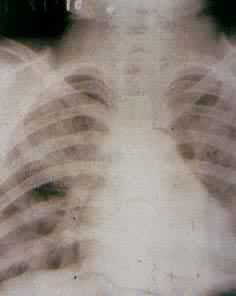

肺部疾病(一) 肺部疾病(二) 大叶肺炎 小叶肺炎 间质性肺炎 肺脓肿(正位) 肺脓肿(侧位) 支气管扩张 浸润性肺结核

肺结核空洞 肺不张